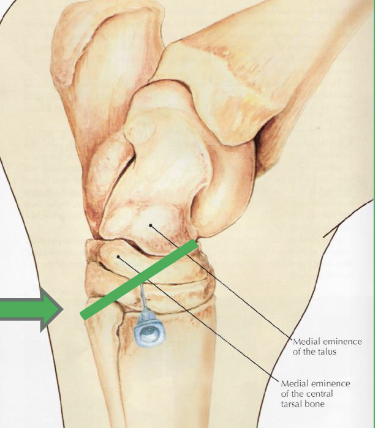

what are the bones of the tarsus

distal tibia, calcaneus + sustentaculum tali (fused), talus (+ medial and lateral trochlea), central tarsal bone, 3rd tarsal bone, 4th tarsal bone, fused 1 & 2 tarsal bone, proximal 2 3 and 4 metatarsal bones

identify middle image

orange- medial trochlear ridge (of talus bone)

purple- lateral trochlear ridge (of talus bone)

blue= sustentaculum tali

green= chestnut

yellow= central tarsal bone

pink= 3rd tarsal bone

light purple= 4th tarsal bone

cream= fused 1 & 2 tarsal bone

red= metatarsal 2 and 4